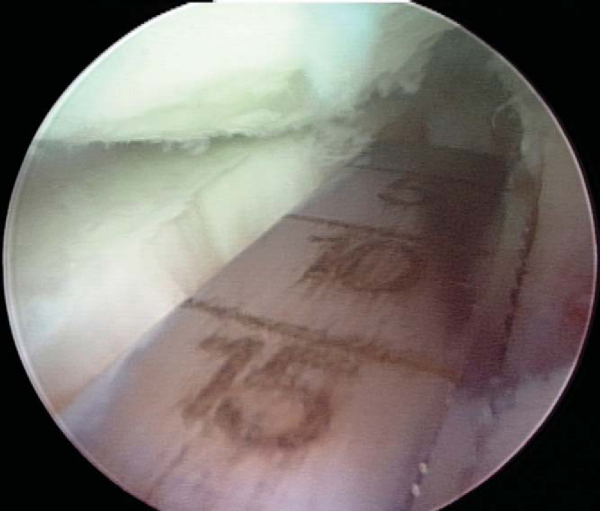

Slot orientation follows the normal anatomy of the meniscus attachment sites. By use of electrocautery, the centers of the anterior and posterior horn attachment sites are connected with a line. With this line as a guide, a 4-mm bur is used to make a reference slot in the tibial plateau. Its height and width will equal the dimensions of the bur, and its alignment in the sagittal plane should parallel the slope of the tibial plateau (

Fig. 47-5

). Slot dimensions should be confirmed by placement of a depth gauge in the reference slot, which also measures the anteroposterior length of the tibial plateau (

Fig. 47-6

). With use of a drill guide, a guide pin is placed just distal and parallel to the reference slot (

Fig. 47-7

) and advanced to but not through the posterior cortex. The pin is subsequently overreamed with a 7- or 8-mm cannulated drill bit (

Fig. 47-8

), again with care taken to maintain the posterior cortex. A box cutter is then used to make a slot 7 to 8 mm wide by 10 mm deep (

Fig. 47-9

), which is smoothed and refined with a 7- to 8-mm rasp to ensure that the bone bridge will slide smoothly into the slot (

Fig. 47-10

).